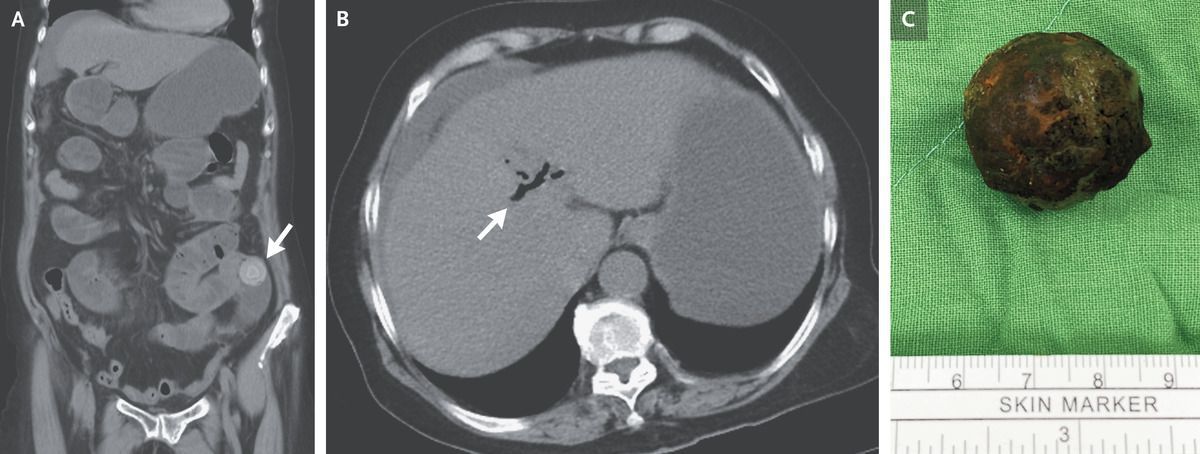

A 74-year-old woman with hypertension presented to the emergency department with a 3-day history of epigastric pain, nausea, vomiting, fever, chills, weakness, and poor appetite. She also reported having had no bowel movements or flatus for the past 2 days. Her blood pressure was 150/128 mm Hg, and her heart rate 144 beats per minute. An abdominal examination revealed tenderness in the periumbilical region and in the left lower quadrant, with voluntary guarding and rebound tenderness. There was no jaundice. Computed tomography of the abdomen revealed obstruction of the ileum caused by a gallstone (Panel A, arrow) and pneumobilia (Panel B, arrow). This combination of radiologic findings — an ectopic gallstone, small-bowel obstruction, and pneumobilia — is known as Rigler’s triad and aroused concern about gallstone ileus. Gallstone ileus is an uncommon cause of small-bowel obstruction, wherein a gallstone passes through a biliary–enteric fistula and becomes impacted within the intestinal lumen. The patient underwent a laparotomy, which confirmed gallstone ileus, and an enterotomy was performed to remove the gallstone (Panel C). Broad-spectrum antibacterial agents were administered after the procedure. The patient was discharged home on postoperative day 11 and was referred for an outpatient cholecystectomy.